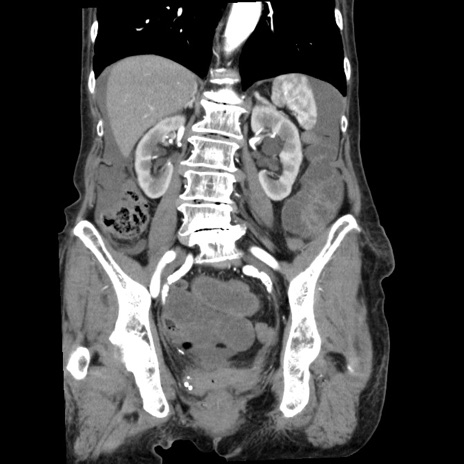

横断像

【症例】80歳代女性

【主訴】腹痛

【現病歴】8時間前から腹痛あり来院。

【既往歴】糖尿病、脂質異常症、子宮体癌にて子宮全摘術

【身体所見】意識清明・会話良好だが腹痛で苦悶様、全腹部にわたって反跳痛と圧痛あり

【データ】WBC 13600、CRP 0.14、LDH 224、CK 90